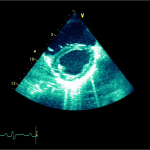

Ecocardiografia transtoracică

- Formaţiune hiperecogenă cu suprafaţa neregulată, care tapetează peretele liber al VD, grosime de 12 mm

- Dispusă de sub planul valvei tricuspide până in apropierea conului de ejecţie al valvei pulmonare

- SIV aplatizat

Ecografia transesofagiană:

Confirmă datele de la ecografia transtoracică